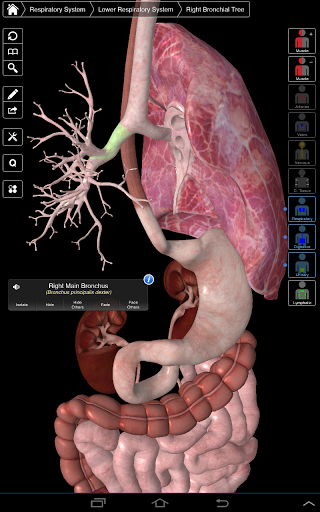

Essential Anatomy 3 reprezentuje najnowsze przełomowe technologie 3D i innowacyjny design. Najnowocześniejszy silnik graficzny 3D, zbudowany na zamówienie przez 3D4Medical od podstaw, zapewnia bardzo dokładny model anatomiczny i zapewnia doskonałą jakość grafiki, której żaden inny konkurent nie jest w stanie osiągnąć.

Aplikacja przedstawia unikalne podejście do uczenia się ogólnej anatomii. Grafika jest nieporównywalna i sprawia, że uczenie się, dzięki wykorzystaniu treści informacyjnej i innowacyjnych funkcji, jest bogatym i wciągającym doświadczeniem.

Ta aplikacja zawiera niezbędną anatomię dla 10 systemów:

⁃Oddechowy

⁃Trawienny

⁃Moczowy

Zawiera także mózg i serce

Essential Anatomy 3 jest responsywny, wizualnie oszałamiający i pozbawiony wysiłku. Aplikacja jest w pełni 3D, co oznacza, że możesz zobaczyć dowolną strukturę anatomiczną w izolacji, a także pod dowolnym kątem.

---- Ponad 4000 bardzo szczegółowych struktur anatomicznych

---- nomenklatura łacińska dla każdej struktury anatomicznej